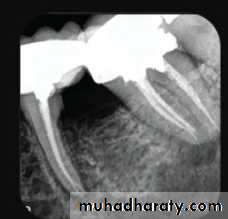

3.Final instrumentation radiograph(Master Cone)

Taken with the final size file /files/

4.Final radiograph (Root canal after Obturation)

Taken after the tooth has been temporized.

Obturation